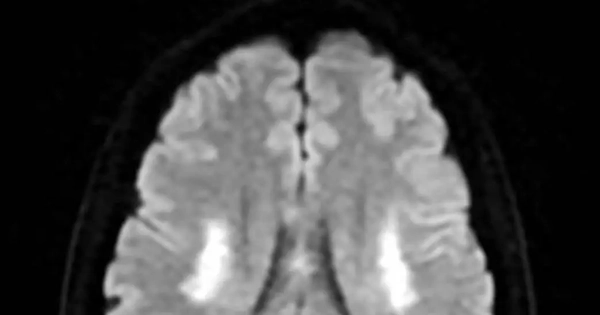

TPO - Người phụ nữ 42 tuổi, đã có hai con trai sinh thường, bất ngờ nhập viện trong tình trạng nói đớ và được chẩn đoán nhồi máu não chỉ vài ngày sau khi tiêm thuốc kích thích buồng trứng trong quy trình thụ tinh trong ống nghiệm.